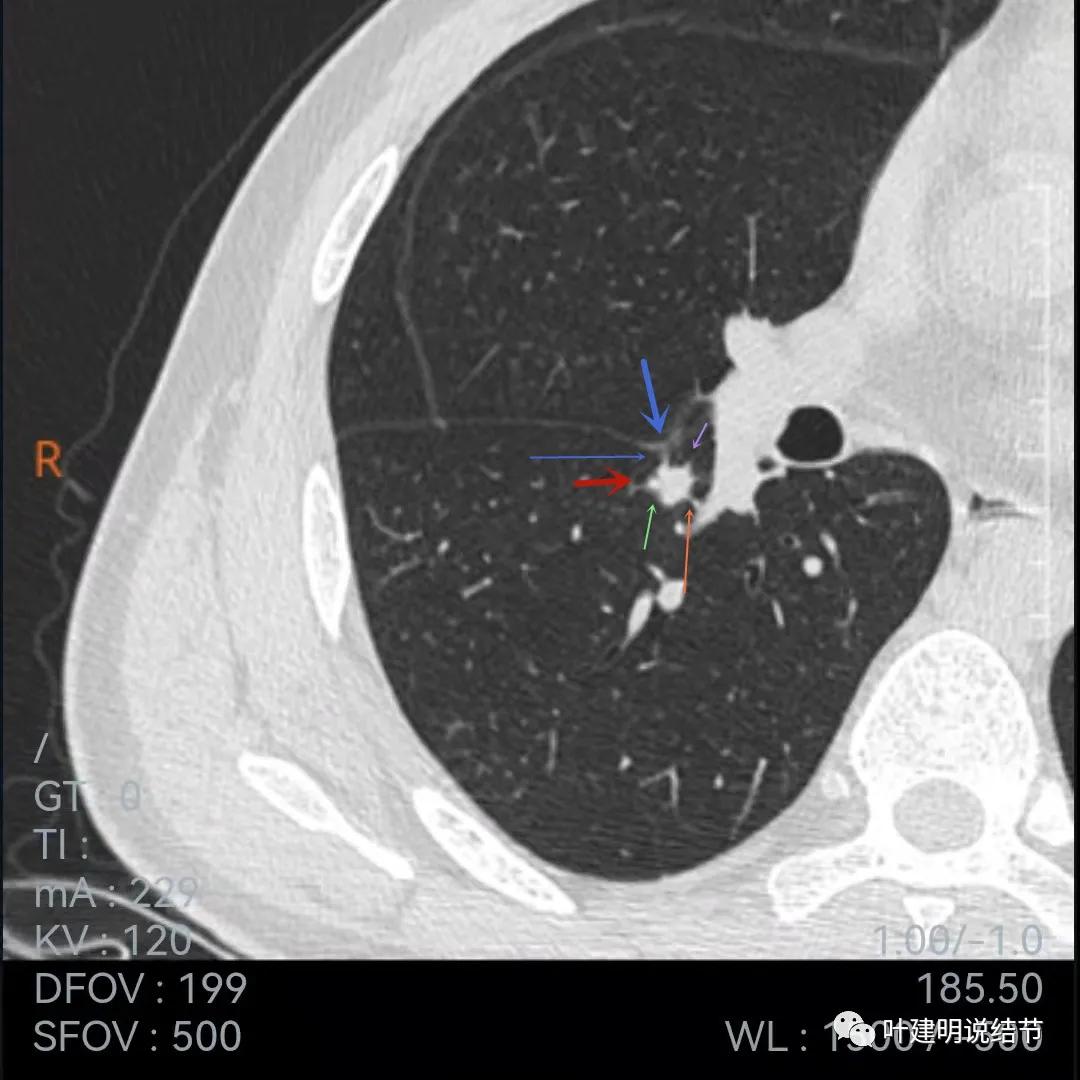

再来看当地医院的靶扫描:

此图不太舒服,胸膜牵拉、表现不平、有微血管征(桔色),但边缘似有少许晕征(绿色),若真是晕征,也是符合肉芽肿性的

上图也示胸膜牵拉、棘突样征,桔色所指似血管进入,但又不太像,增粗的淋巴结管?血管边的是淋巴结吗?不清楚,先不管它

病灶表面不平

病灶密度略不均